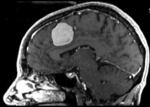

Slicer Registration Library Case #1: Follow-up MRI of Brain Tumor

This case contains a baseline-followup pair of brain MRI. Goal is to align the follow-up image with the reference/baseline scan to assess changes, particularly in the tumor region.

MRI, brain, head, intra-subject, meningioma